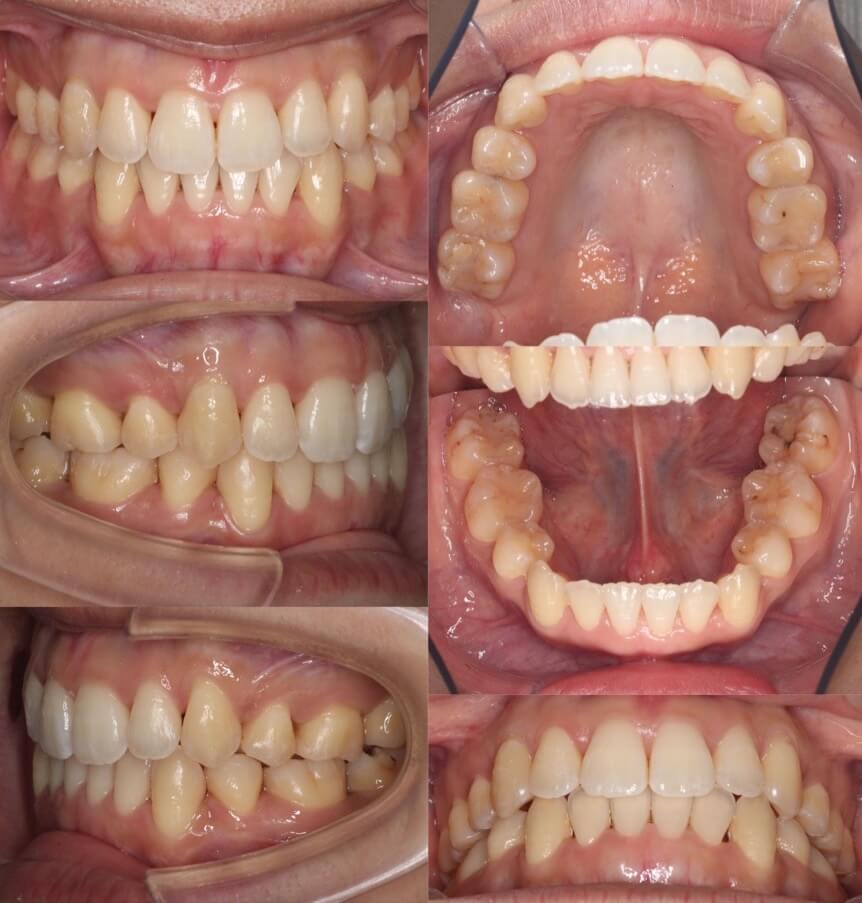

「前歯の角度が変化」

20代女性・ハーフリンガル装置・下あご後退型

前歯が前に傾斜している(倒れている)上下顎前突症例です。抜歯スペースに前歯を押し込むだけで、口元の突出が改善できる割と単純なケースになります。治療後は上下の前歯の角度も内向きに変わりました。

<症例概要>

主訴:前歯を引っ込めたい

年齢・性別:20代女性

住まい:千葉県佐倉市

症状:下顎後退・上下顎前歯唇側傾斜

治療方針:抜歯空隙の閉鎖(最大固定)

治療装置:ハーフリンガル矯正装置(上のみ裏側装置)

固定:歯科矯正用アンカースクリュー(口蓋側壁x2)

抜歯:上下第一小臼歯

治療期間:1年10か月

リテーナー:上下プレートタイプ+クリアタタイプ+フィックスタイプ

治療費用:1,4950,000(税込)

代表的副作用:痛み・治療後の後戻り・歯根吸収・歯髄壊死・歯肉退縮